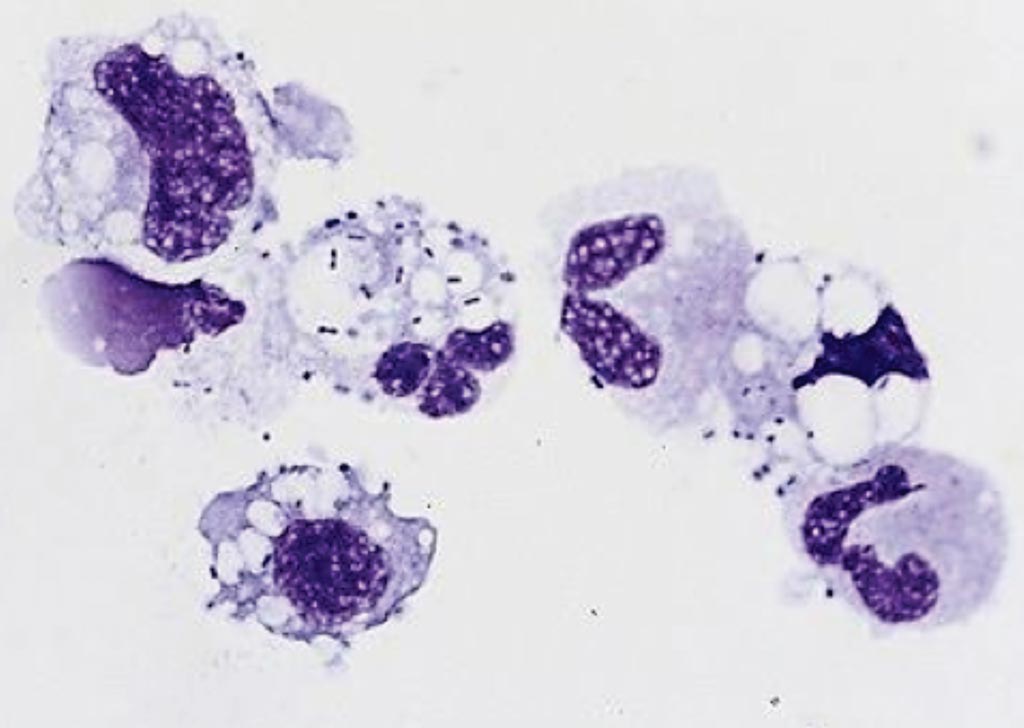

Mesothelial cells

knowt flashcard image